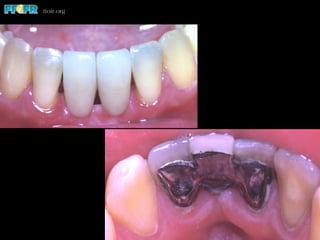

RBP Caries

(Evaluated in 22 Studies)

•  242 of 3426 prostheses had caries

•  Mean of 7%

•  Range from 0.0 to 12%

•  None in 9 studies (2 mos. - 59 mos.)

•  < 2% in 6 studies (2 mos. - 5 yrs. 8 mos.)

•  2.5 - 12% in 7 studies ( 2.5 - 10 yrs.)

•  Most associated with debonding